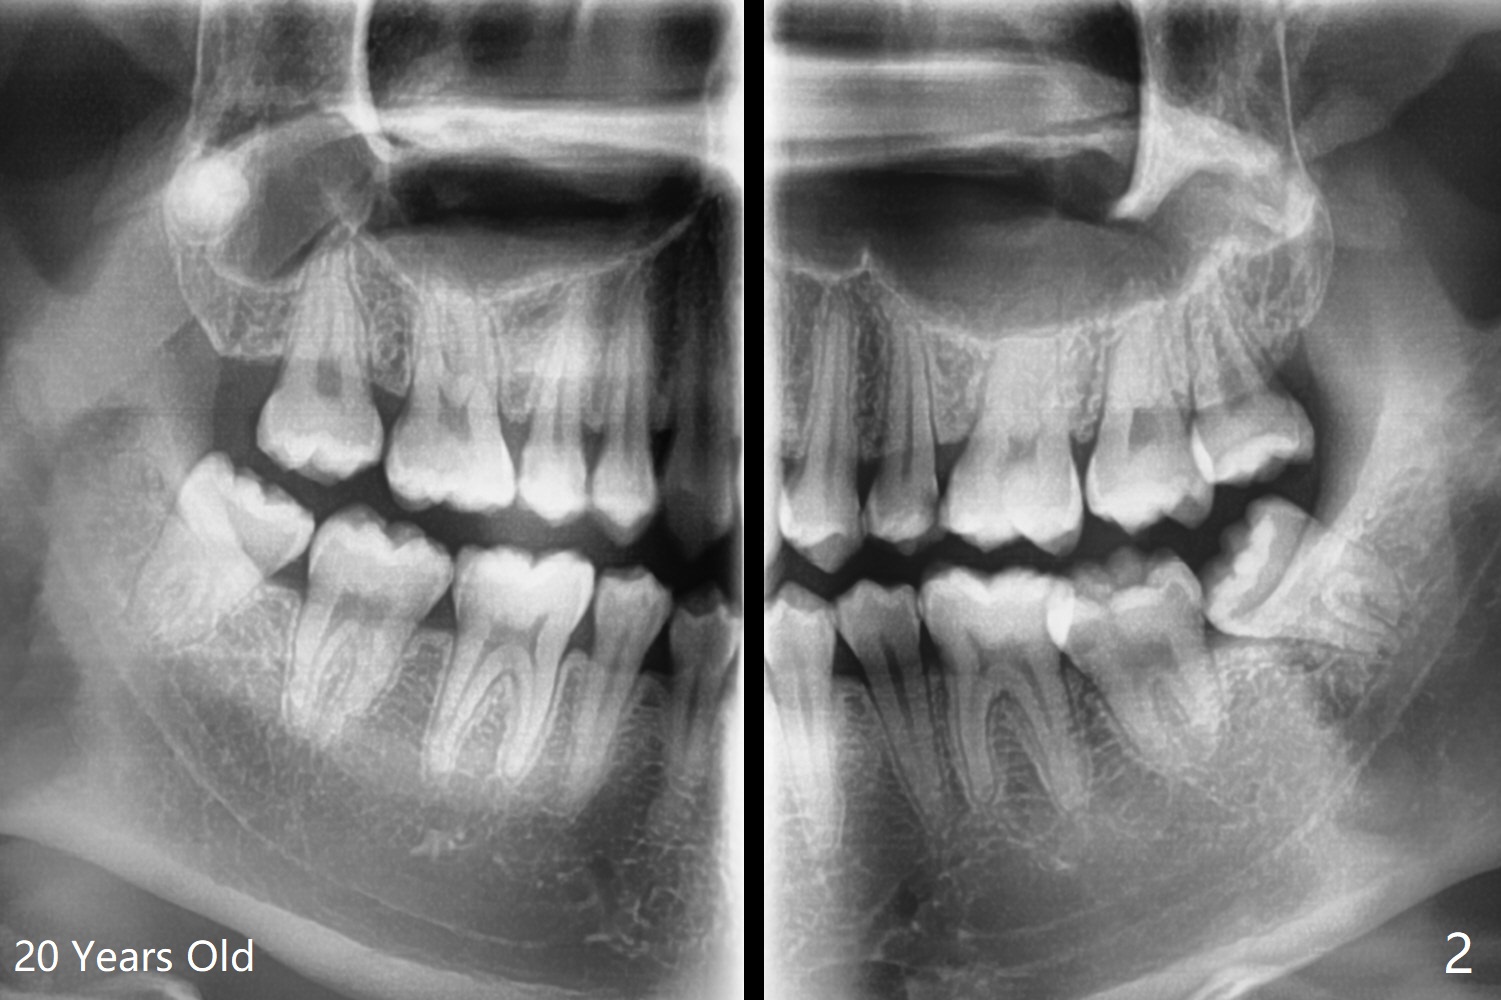

A 20-year-old man has been our patient irregularly since the age of 13. His mother reported that he did not brush well, probably related to gag reflex. Panoramus is taken at the ages of 16 and 20 (Fig.1,2). In fact a primitive cyst forms (Fig.1) before calcification of the impacted upper right 3rd molar (dentigerous cyst, Fig.2). After extraction and enucleation of the cyst, Augma will be injected into the cavitation, followed by Osteogen plug.